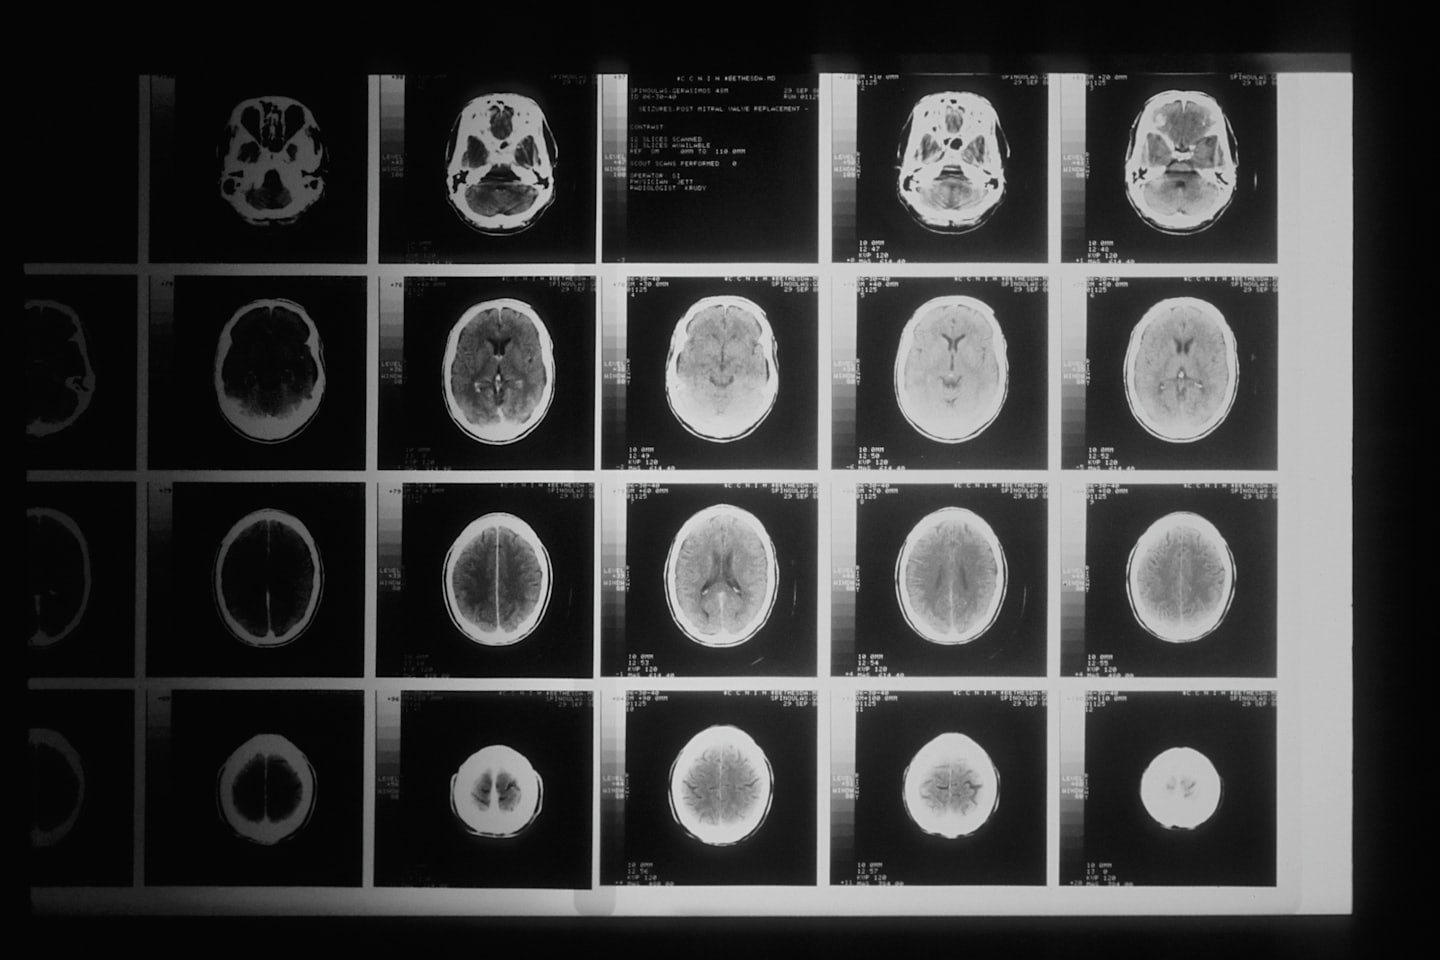

Bildgebung

Hochauflösendes Röntgen und Sonographie zur präzisen Diagnose.